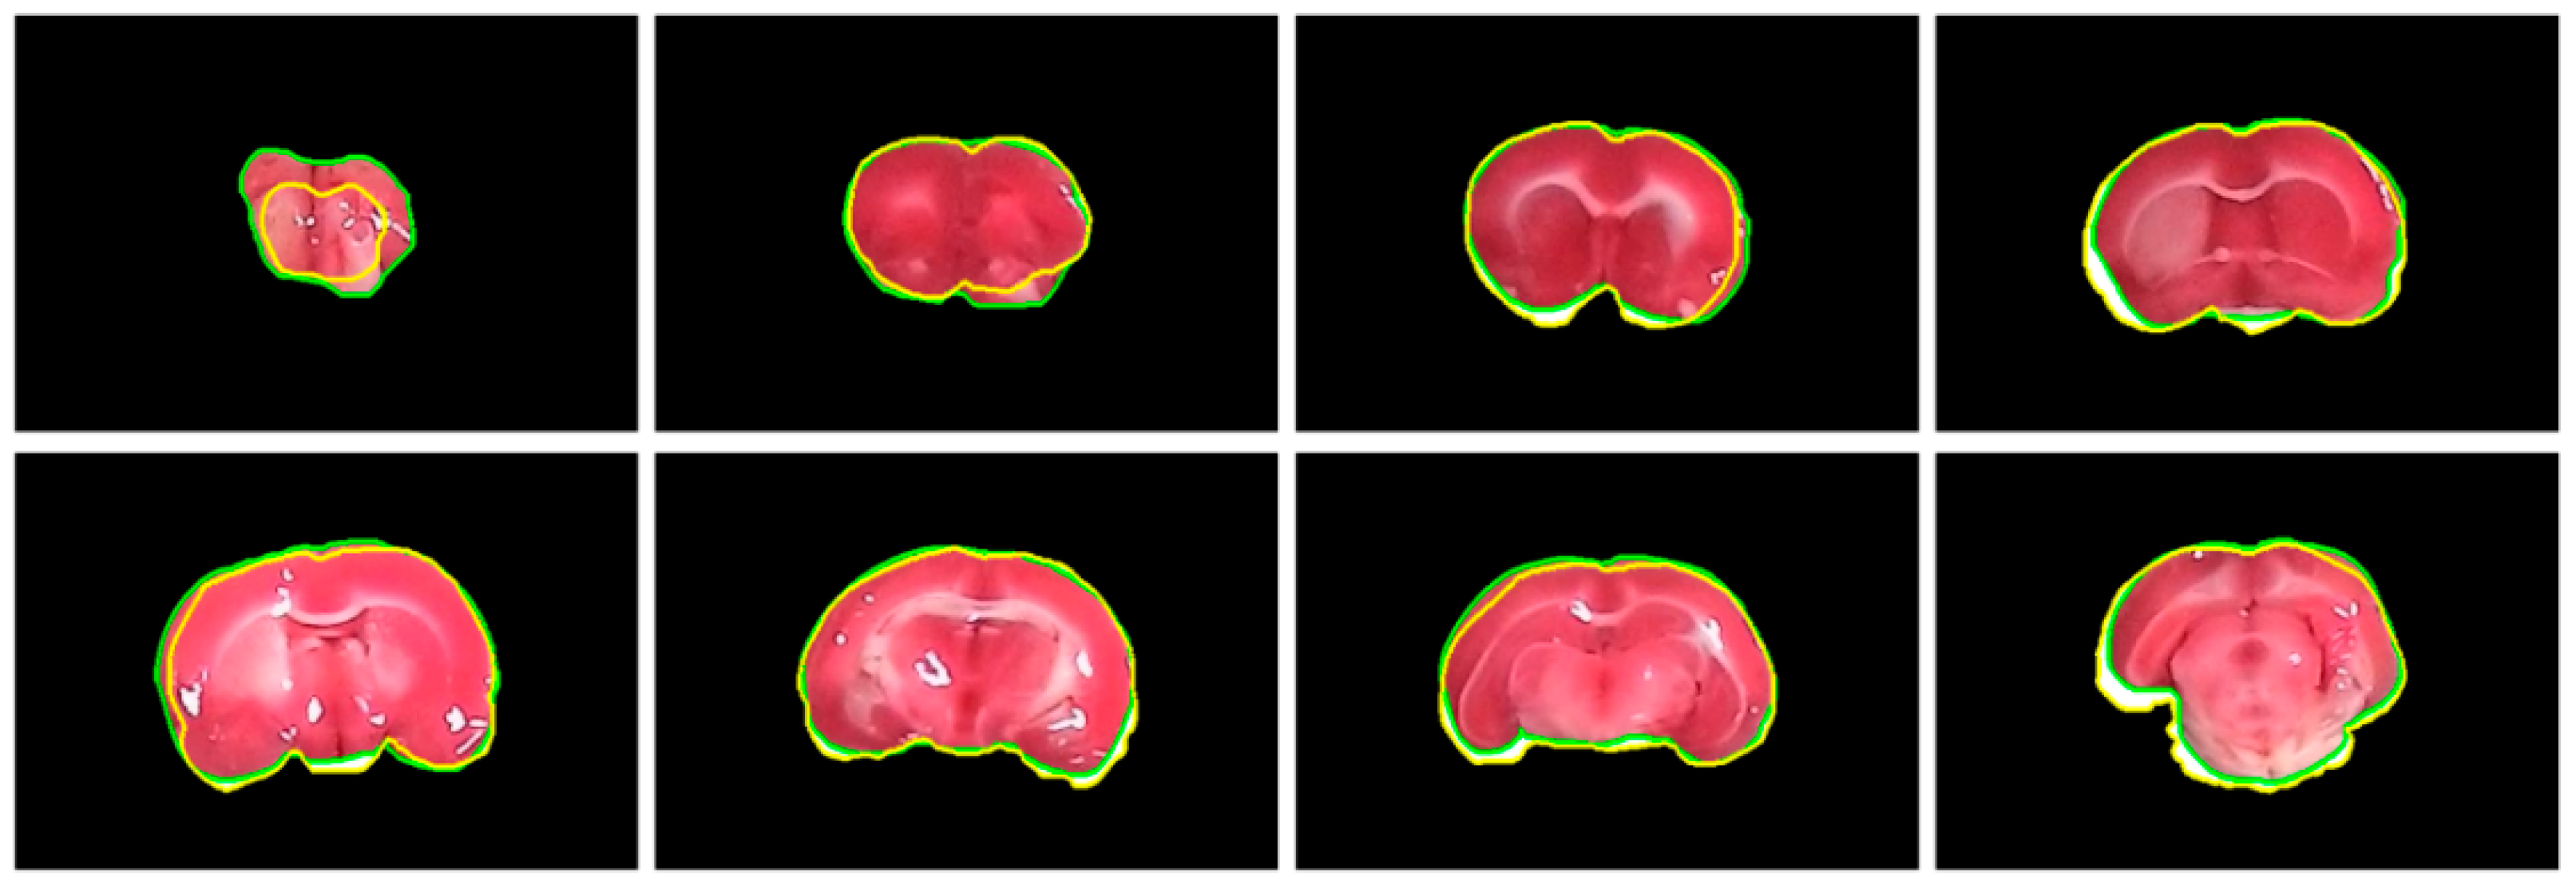

2. Brain Extraction

2.1. Challenges

- In addition to the stained rat brain slices, there are a scale and a label indicating the status of the subject being experimented, both of which need to be eliminated.

- The shape of the brains is irregular with broken and ambiguous boundaries.

- The colors of the brain slices range from white, pink, to cardinal with a nonuniform distribution.

- There are some bright stains on the brain regions due to the reflection of the moisture in the organ.

- The background is not clean and simple with a varying intensity distribution and a complicated pattern of light reflection.

2.6. Final Brain Segmentation

4.3. Evaluation of Rat Brain Extraction